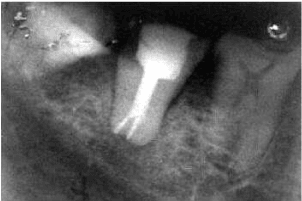

A 20-year-old healthy male patient reported to Department of Conservative dentistry and Endodontics with pain in lower left posterior region. Intraoral examination revealed the deep proximal caries in tooth #37 which was sensitive to percussion and palpation. Intraoral periapical radiograph of tooth #37showed huge pulp chamber extending beyond the CEJ reaching the furcation in the apical third region (Figure 6). Two short roots were seen at the furcation area in the apical third indicating hypertaurodontism. The contralateral tooth showed no such abberation. The diagnosis of irrevesible pulpitis with apical periodontitis and unilateral hypertaurodontism was made. Similar treatment procedure was carried out as in case 1 and final radiograph was taken that confirmed well obturated root canals in tooth #37 (Figure 7).

Figure 6: Pre- operative Radiograph of #37.